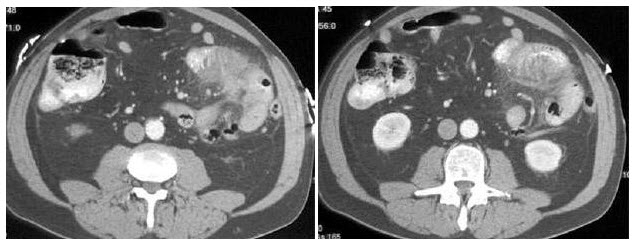

女,54岁,腰背部隐痛不适1月余,根据所示图像,最可能的诊断是()

A.左侧单纯性肾囊肿,右肾未见异常

B.左侧肾盂积水合并右侧肾血管平滑肌脂肪瘤

C.左侧单纯性肾囊肿合并右侧肾癌

D.左侧肾盂积水合并右侧肾癌

E.左侧单纯性肾囊肿合并右侧肾血管平滑肌脂肪瘤